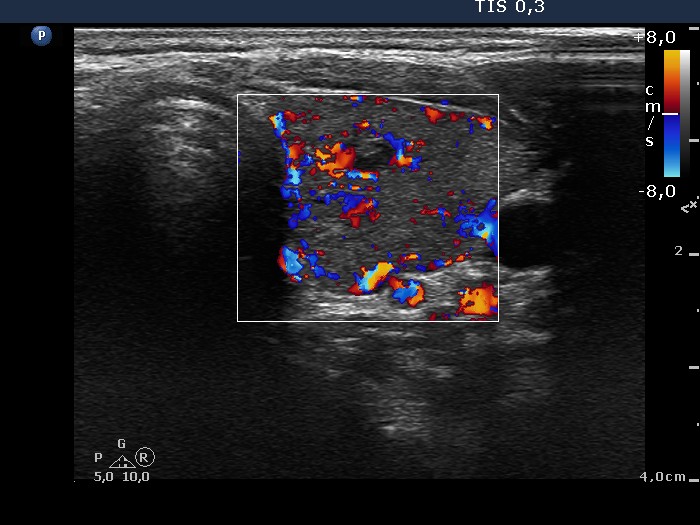

Clinical data: A 31-year-old woman was referred for evaluation of a suspicious nodule. She was treated for Graves' hyperthyroidism for 15 months. At the time of the discontinuation of the thyrostatic therapy, an ultrasound examination was performed, and a hypoechogenic nodule with microcalcifications was described.

Ultrasonography: The thyroid was minimally-moderately hypoechogenic with several insignificant discrete areas. There were two hypoechogenic small lesions close to each other within the left lobe. The larger one displayed hyperechogenic lines and figures in the back wall of cystic areas; these are optical artifacts caused by posterior back wall enhancement.

Cytology was performed from the hypoechogenic lesion in the left lobe and resulted in benign lesion with hormonal influences.

Comment. The optical artifacts caused by posterior back wall enhancement should not be interpreted as microcalcifications.